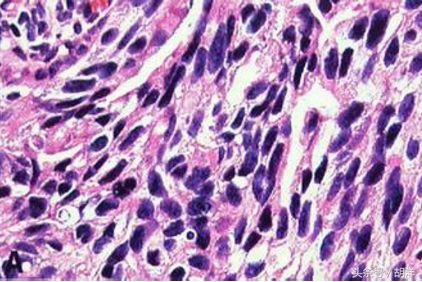

低分化肿瘤:癌细胞分化程度更低,近似来源组织的不成熟形态,如低分化腺癌,腺管,腺泡结构基本消失。

未分化肿瘤:瘤细胞分化程度极差,往往呈弥漫性排列,无聚集倾向,如能断定为来源上皮细胞,则不能肯定是来自鳞状上皮或腺上皮者,则称为未分化癌。肿瘤细胞分化程度愈低,其恶性程度越高,发展越快,转移越早,对放化疗越敏感。